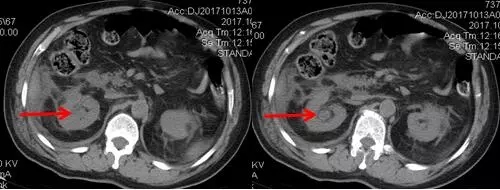

入院后經(jīng)細致檢查,診斷其為泌尿系結(jié)石,右腎積水,右輸尿管梗阻,30余年前曾在錢糧湖醫(yī)院行闌尾切除術(shù)及腸梗阻手術(shù)。由于患者右腎為重復(fù)腎合并結(jié)石,解剖結(jié)構(gòu)和病情極其復(fù)雜。泌尿外科周旭陽主任組織科室專家進行術(shù)前討論,決定在充分抗感染治療的基礎(chǔ)上行經(jīng)皮腎鏡鈥激光碎石術(shù)。

術(shù)后CT,箭頭所指為腎結(jié)石被徹底清除

三日后,曾奶奶病情逐漸穩(wěn)定,各項感染指標逐漸恢復(fù)正常,復(fù)查CT顯示腎結(jié)石已經(jīng)被完全清除,現(xiàn)已康復(fù)出院。就此,困擾曾奶奶多年,反復(fù)感染差點致命的腎結(jié)石頑疾被徹底治愈。曾奶奶全家人對于愛康醫(yī)院泌尿外科專家高超的碎石取石手術(shù)技藝更是贊許有加,對泌尿外科團隊的工作給予衷心感謝和高度評價。